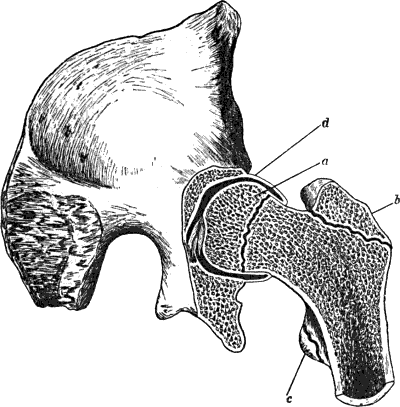

60.Section through Hip-Joint to show Epiphyses at Upper End of Femur, and their relation to the Joint130

129.Innominate Bone and Upper End of Femur from a case of Congenital Dislocation of Hip250